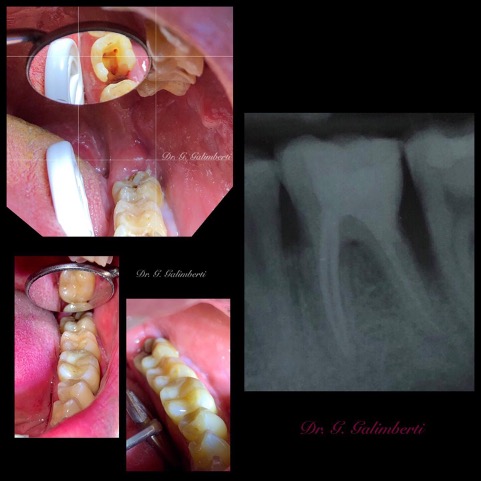

Una corretta terapia canalare con un perfetto sigillo a livello degli apici delle radici è fondamentale. I denti devitalizzati impropriamente possono creare ulteriori problemi che poi andranno a ripercuotersi sulle cure effettuate successivamente come le ricostruzioni e le corone protesiche con conseguente fallimento del piano terapeutico.

Capita spesso di incontrare denti già devitalizzati in maniera impropria che necessitano, seppur asintomatici, di essere ritrattati per evitare che i granulomi infetti visibili radiograficamente si evolvano riassorbendo tutto l’osso sottostante.

L’endodonzia è una branca complessa dell’odontoiatria, richiede precisione, una lunga curva di apprendimento oltre che all’imprescindibile capacità di utilizzare degli ingrandimenti adeguati. Il Dott. Galimberti Gabriele, esperto in endodonzia, è arrivato a trattare più di 1200 denti all’anno.